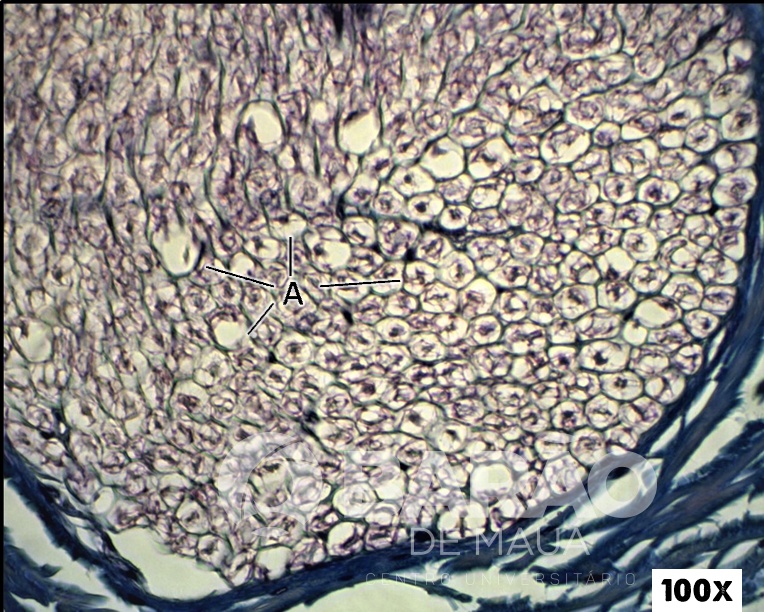

Nervo - A = axônios mielinizados - Coloração: TM

Nervo - A = axônios mielinizados - Coloração: TM.